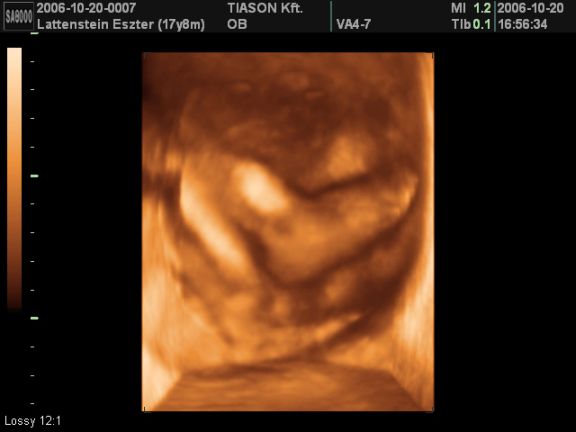

ez pedig a lábia:)